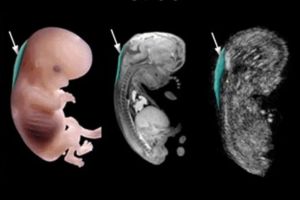

سونوگرافی آنومالی جنین یکی از مهمترین مراحل غربالگری دوران بارداری است که معمولاً در هفتههای ۱۸ تا ۲۲ بارداری انجام میشود. هدف اصلی این روش بررسی دقیق وضعیت و ساختار ارگانهای حیاتی جنین شامل مغز، ستون فقرات، قلب، کلیهها، دستگاه گوارش و اندامهاست تا ناهنجاریهای مادرزادی و نقائص احتمالی از جمله ناهنجاریهای ساختاری، مشکلات رشد یا اختلالات کروموزومی به موقع شناسایی شوند. با استفاده از دستگاههای سونوگرافی پیشرفته و تیم متخصص تصاویر واضح و تخصصی تهیه شده و هرگونه مشکل احتمالی به پزشک گزارش میشود تا تصمیمگیری دقیق در ادامه روند بارداری و برنامهریزی درمانی صورت گیرد. این سونوگرافی معمولاً بدون درد است و نقش بسیار مهمی در حفظ سلامت مادر و جنین ایفا میکند.